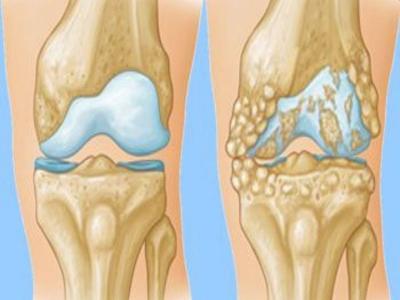

गठिया के दो तरह के होते हैं, ऑस्टियोआर्थराइटिस और रूमेटाइड आर्थराइटिस। ऑस्टियोआर्थराइटिस आर्थराइटिस का ही एक रूप है जिसमें एक या एक से ज्यादा जोड़ों के कार्टिलेज टूट जाते हैं या घिसते रहते हैं। इस रोग में हड्डियों के कमजोर होने के कारण जोड़ों में दर्द शुरू हो जाता है। इसमें आपको अपनी उंगलियों, घुटनों या कूल्हों में दर्द महसूस हो सकता है।